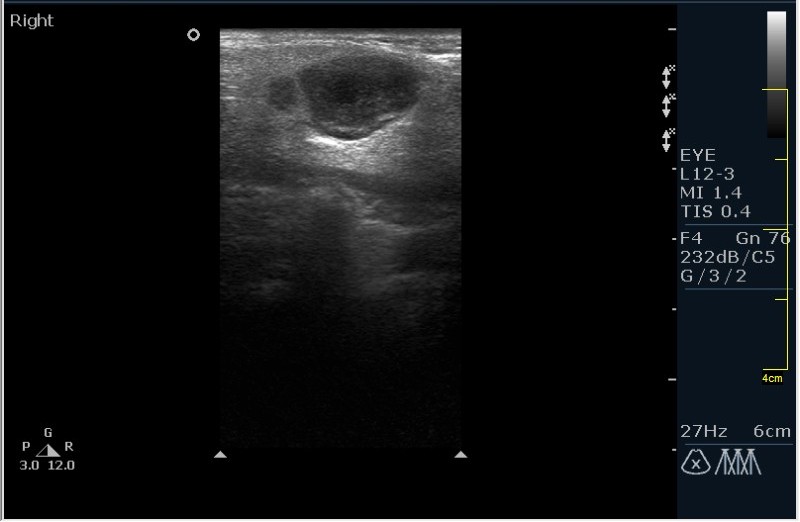

Мужчина 68 лет, направлен на УЗИ правой слюнной железы. Жалобы на пальпируемое, малоболезненное плотное образование за правым ухом.

Солидное!!!! Я тоже ТАБ хотел сделать, но ЛОР заказал КТ... А какие мысли будут?

Первая мысль о очаговом воспалении, деструктивной фазе, но нет клиники.

Тумор?

Клиники нет, тумор на первом месте. В принципе КТ (или МРТ) заказывают для диффиренцировки зло/добро. Плюс посмотреть есть ли локальное растпространение. Но в данном случае я думаю УЗИ с ТАБ было бы достаточно.